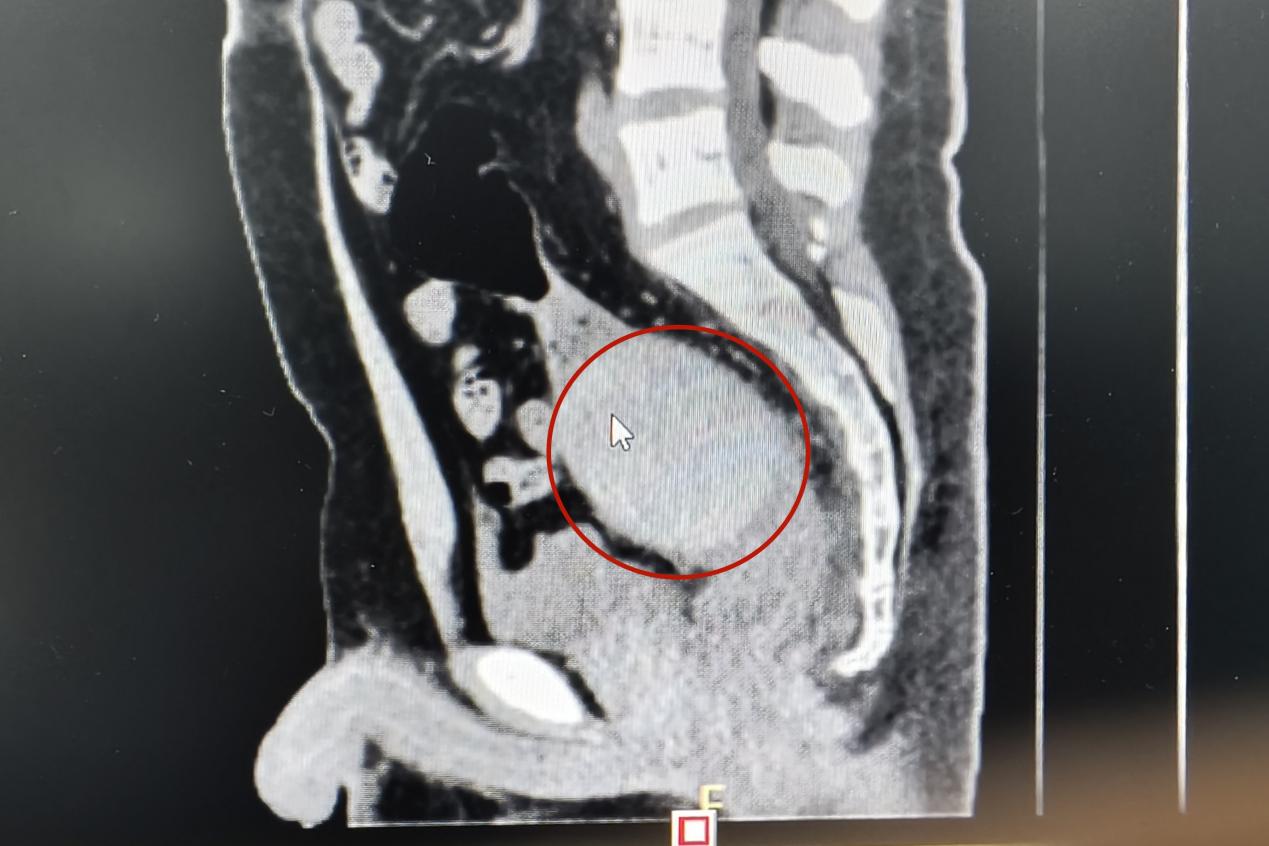

當(dāng)天下午,一名青年男子來到衡陽市中心醫(yī)院肛腸外科門診就醫(yī),稱肛門內(nèi)有異物,肚子疼得很。李祥樂仔細(xì)詢問病情,男子卻總是支支吾吾??此?/span>表情痛苦,李祥樂便讓他躺到治療床上,對(duì)其進(jìn)行了肛門指檢。“你這個(gè)異物卡得很深,指檢觸不到,需要馬上做個(gè)CT明確位置?!崩钕闃芬贿吀嬷颊咭贿呍儐枺斑@個(gè)東西卡進(jìn)去多久了?”得知是昨晚發(fā)生的事,李祥樂心頭一驚,卻表面平和地安慰患者道:“沒事的,到醫(yī)院來你就放寬心了,等檢查結(jié)果出來我們想辦法給你取”。CT結(jié)果顯示患者異物位于直腸與乙狀結(jié)腸交界處,位置特殊,加之卡頓時(shí)間長(zhǎng),取的過程中腸道破裂出血的風(fēng)險(xiǎn)隨之增加。“我可以嘗試給你經(jīng)肛門取,但是如果取不出來那就需要進(jìn)行腹腔手術(shù)了”。